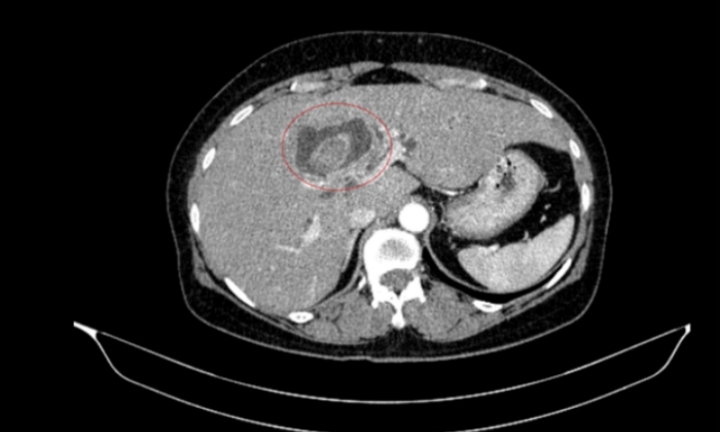

Bệnh nhân 59 tuổi nhập viện vì vàng da, ngứa kéo dài, được phát hiện đồng thời ung thư đại tràng phải và ung thư đường mật trong gan.